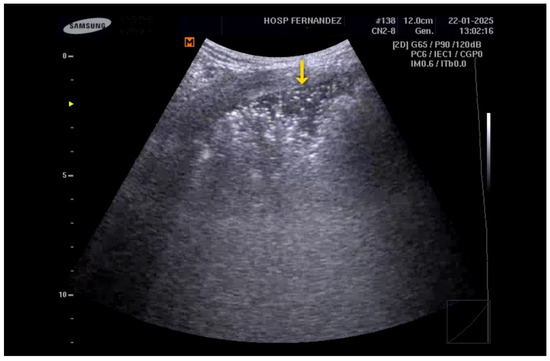

- Multiple B-Lines: These appear in a diffuse, inhomogeneous distribution and are critical for ILD diagnosis.

- Pleural Line Abnormalities: These may include thickening, irregularities, and fragmentation of the pleural line.

- Pinal-Fernandez, I.; Pallisa-Nuñez, E.; Selva-O’Callaghan, A.; Castella-Fierro, E.; SimeOn-Aznar, C.P.; Fonollosa-Pla, V.; Vilardell-Tarres, M. Pleural irregularity, a new ultrasound sign for the study of interstitial lung disease in systemic sclerosis and antisynthetase syndrome. Clin. Exp. Rheumatol. 2015, 33 (Suppl. S91), S136–S141. [Google Scholar]